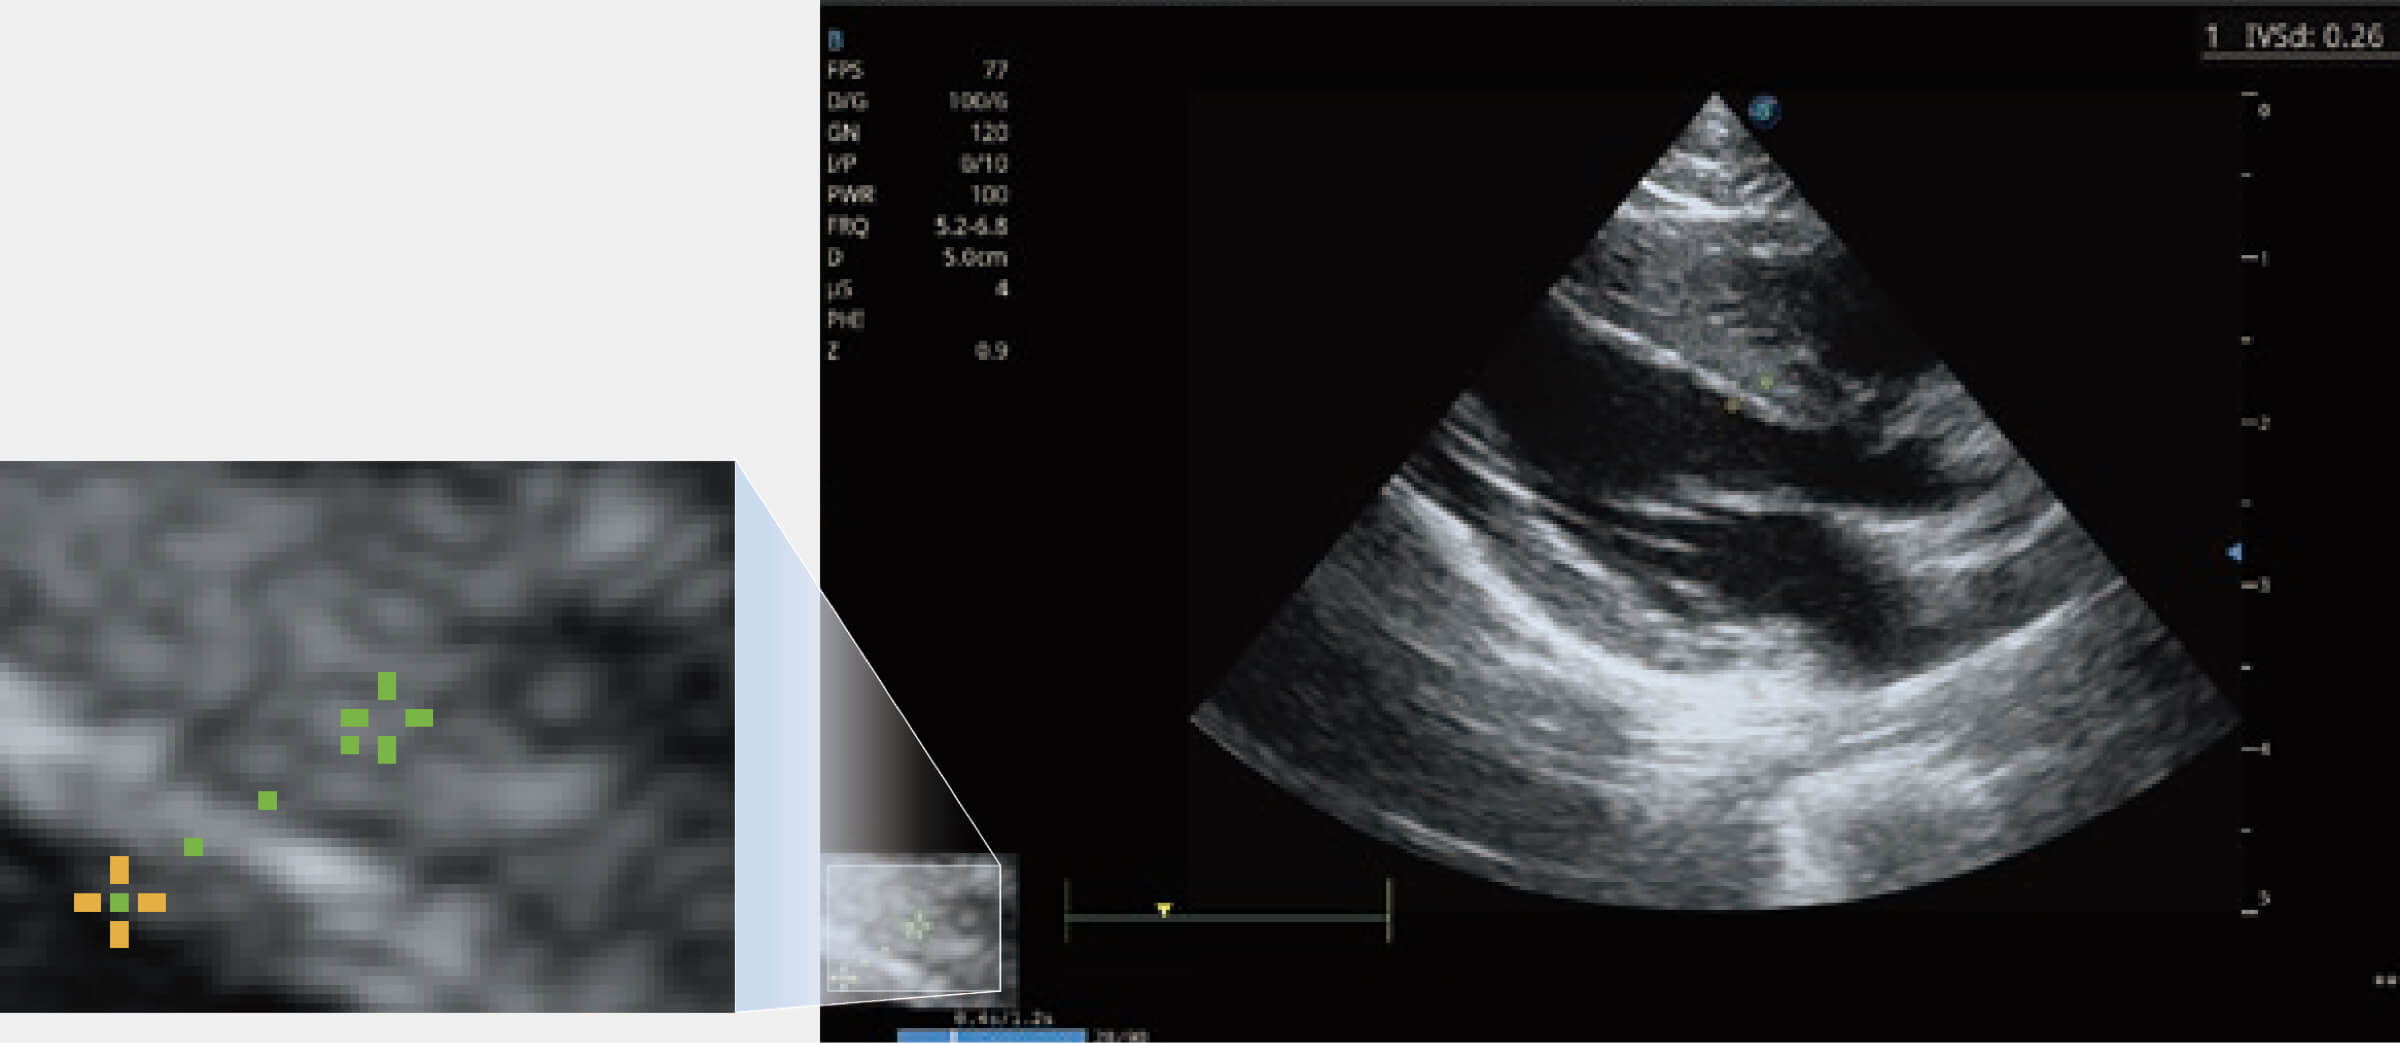

通过360度任意调节3条M型取样线,在同一心动周期上观察心脏不同位置的运动曲线,得到准确的心功能测量数据,有效评估心肌运动及左心室功能。